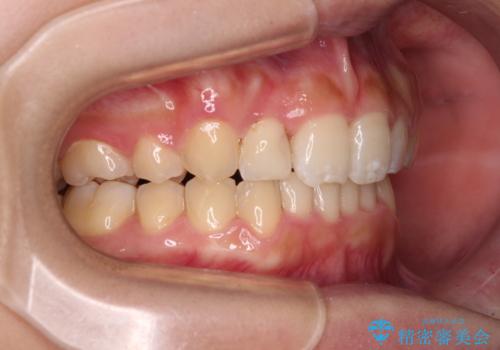

- 上顎の重なっている前歯を気にして来院された患者様です。

八重歯改善には抜歯が必要で、八重歯の移動量が多く、更には右側にずれている正中を改善する必要がありました。

インビザライン単体での治療は困難と判断し、補助装置により八重歯移動後にインビザラインを用いることとしました。

インビザラインでは治療期間が延びることが予想されたため、ワイヤー矯正を提案しましたが、セラミッククラウンが多く、壊すあるいは傷が付く可能性があることから、長期間であってもインビザラインを選択されました。